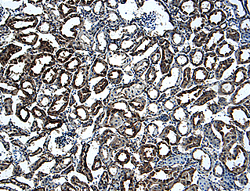

- TWEAK R/TNFRSF12 in Mouse Kidney. TWEAK R/TNFRSF12 was detected in perfusion fixed frozen sections of mouse kidney using 15 µg/mL Goat Anti-Mouse TWEAK R/TNFRSF12 Antigen Affinity-purified Polyclonal Antibody (Catalog # AF1610) overnight at 4 °C. Tissue was stained with the Anti-Goat HRP-DAB Cell & Tissue Staining Kit (brown; Catalog # CTS008) and counterstained with hematoxylin (blue). View our protocol for Chromogenic IHC Staining of Frozen Tissue Sections.